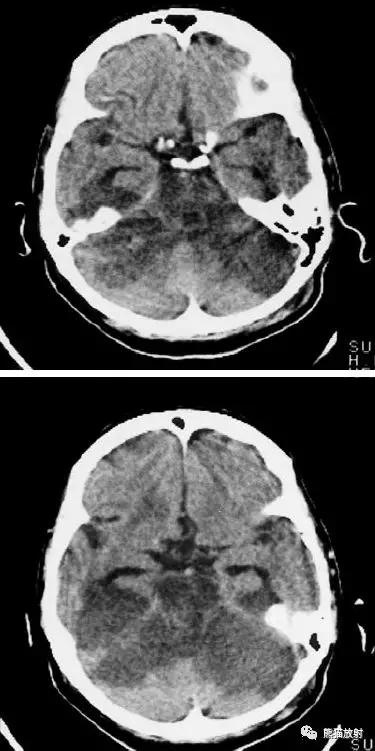

左侧大脑中动脉区完全梗死,对邻近的侧脑室产生占位效应;右侧可见其他较小的缺血性低密度区。

右侧大脑前、中动脉供血区梗死,可见明显占位效应。